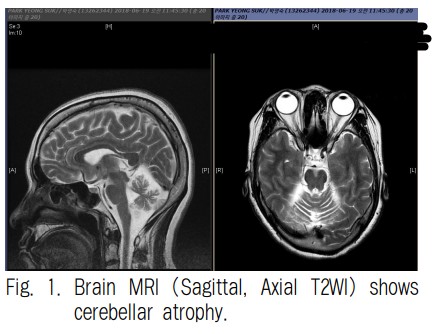

2) 영상 검사 : 뇌 MRI, 척수 MRI, SPECT 등의 영상 검사를 통해 뇌와 척수의 이상을 확인합니다.